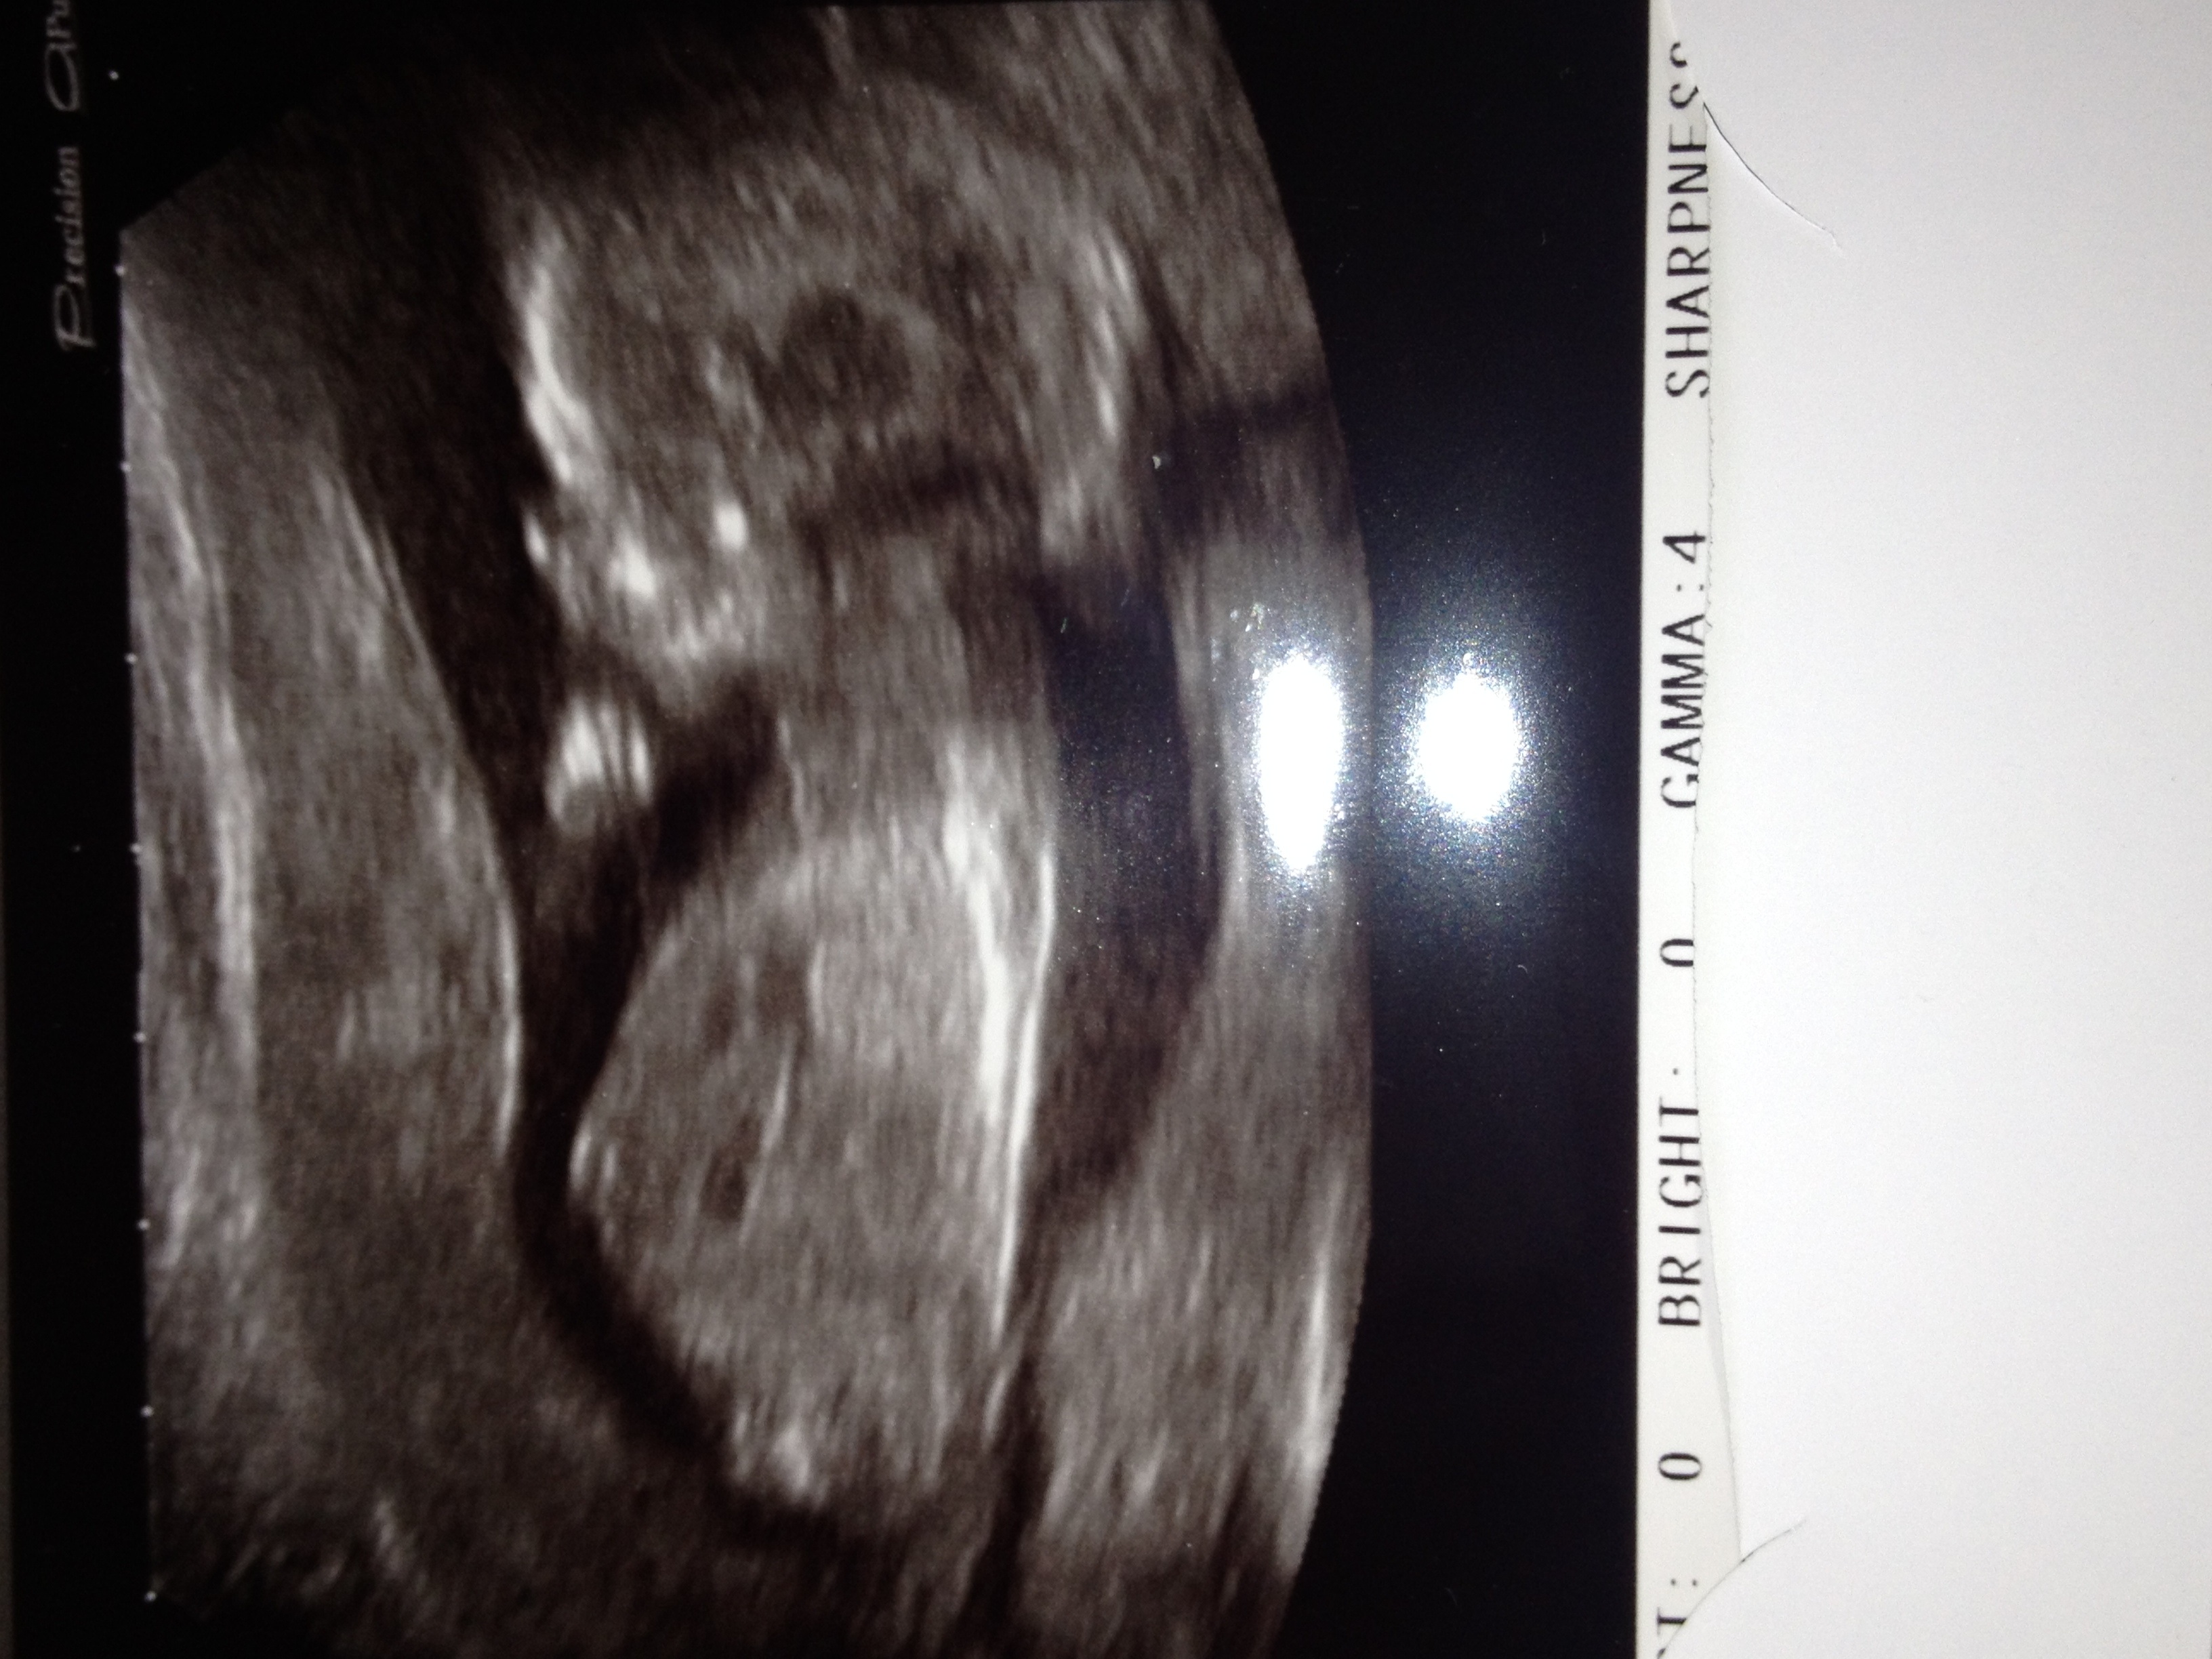

14 week scan pic boy or girl!!!!